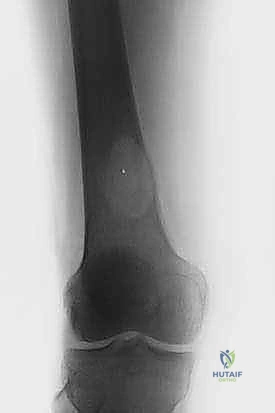

| جسم عظم الفخذ أو الساق | كسر مرضي كامل أثناء التحميل. | التثبيت بمسمار نخاعي تشابكي (Intramedullary Nailing). |

| الطرف العلوي (عظم العضد) | فقدان وظيفة الذراع، ألم شديد. | التثبيت بشرائح ومسامير أو مسمار نخاعي مع استخدام أسمنت عظمي. |